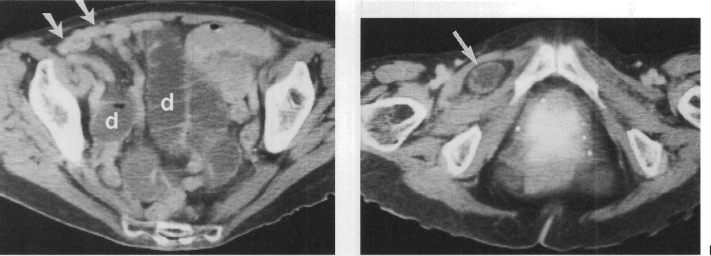

64 anos, mulher com Dor abdominal intensa

Hérnia de spiegel com sinais de estrangulamento

Colo herniário na linha semilunar, separando os músculos reto abdominal e transverso

Hérnias de spiegel tem alto risco de encarceramento (margens afiadas).

Neste caso a hérnia continha gordura omental e mostrava sinais de estrangulamento: densificação da gordura e liquido no interior do saco herniário.